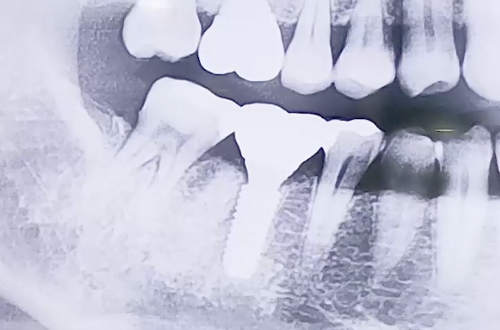

AFTER

때문에 발치 후 임플란트를 시행하기로 하였으나, 발치한 자리 가운데에

때문에 염증을 피해 살짝 옆쪽으로 심고, 염증 부분은 치료한 뒤

뼈이식으로 정리해 드리는 방향으로 치료해 드렸습니다.